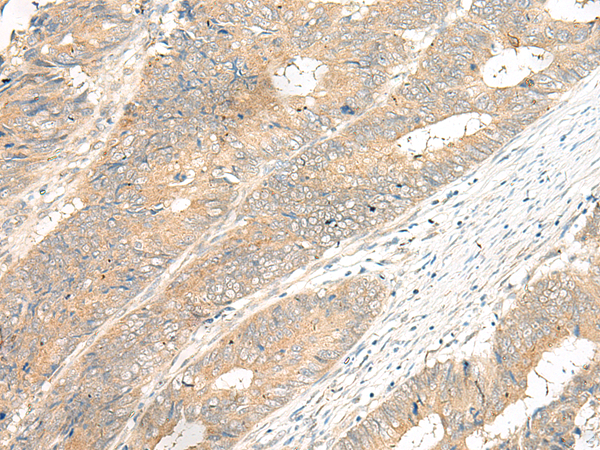

分类: 科研抗体货号: P06598别名:应用: IHC反应种属: Human, Mouse, Rat

分类: 科研抗体货号: P06587别名:应用: WB,IHC反应种属: Human

分类: 科研抗体货号: P06596别名: PGR8应用: WB,IHC反应种属: Human

分类: 科研抗体货号: P06618别名:应用: IHC反应种属: Human, Mouse

分类: 科研抗体货号: P06583别名: GP210; POM210应用: IHC反应种属: Human, Mouse, Rat

分类: 科研抗体货号: P06594别名: GT01; PGR4; BMIQ10; GPR120; GPR129; O3FAR1应用: IHC反应种属: Human

分类: 科研抗体货号: P06611别名:应用: IHC反应种属: Human

分类: 科研抗体货号: P06593别名: GPCR12; GPCR21; PPP1R84应用: IHC反应种属: Human, Mouse, Rat